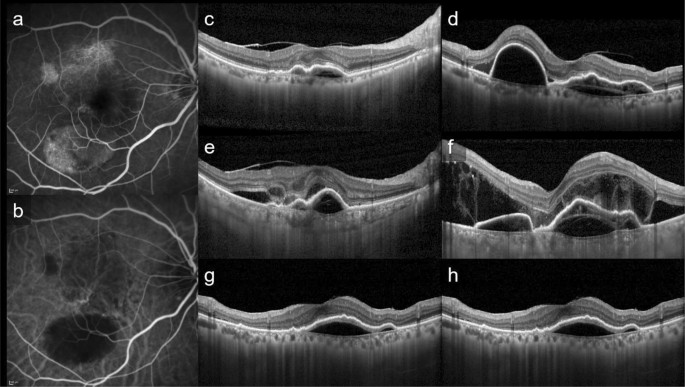

This is a representative case of PAEM+. Fluorescein angiography (a), indocyanine green angiography (b), and horizontal (c, e, g) and vertical (d, f, h) line of optic coherence tomography images of patients at baseline (c, d), 3 days follow-up (e, f) and 1 month follow-up (g, h) after photodynamic therapy (PDT). 82-year-old-female with polypoidal choroidal vasculopathy in the light eye. Central retinal thickness was 361 µm at baseline, 538 µm (+ 49.0%) at 3 days, 334 µm (− 7.5%) at 1 month after PDT. Central choroidal thickness was 135 µm at baseline, 270 µm (+ 100.0%) at 3 days, 126 µm (− 6.7%) at 1 month after PDT. The subretinal fluid increased at 3 days follow-up, with complete resolution at 1 month follow-up. The bacillary detachment was also seen only at 3 days follow-up.